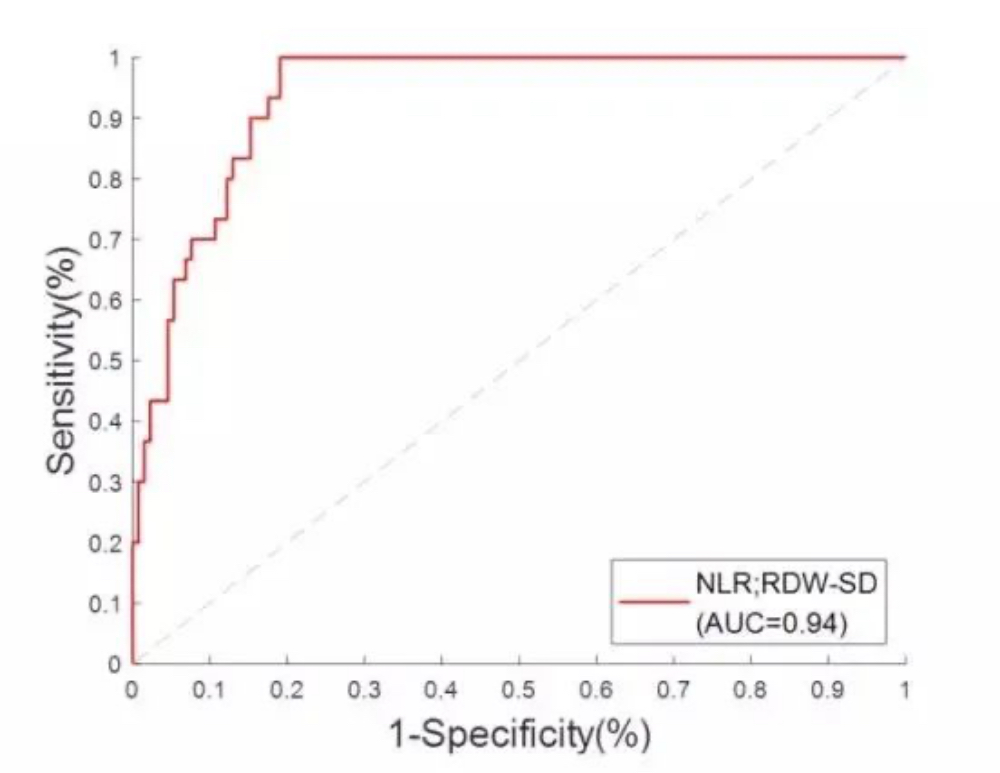

In view of the obvious RDW-SD differences between moderate and severe cases, a linear regression of NLR and RDW-SD is established, with an AUC at 0.94. When the cut-off value is 1.06, the sensitivity of distinguishing moderate cases from severe cases is 90%, and the specificity is 84.7%. That is, when its NLR & RDW-SD result is greater than 1.06, it is highly possible that the patient should be monitored closely in case of further deterioration and admitted to ICU if needed. This result can provide valuable information to facilitate faster, more accurate clinical decisions that leads to improved patient outcomes.

With NLR and RDW-SD results in focus, a linear regression and ROC curve analysis were introduced in order to establish the NLR & RDW-SD parameter as an indicator to identify severe cases. With an AUC reaching 0.94, this parameter can provide useful information to help doctors decide which category the patient should be put into and what corresponding treatment the patient should receive. However, it must be pointed out that this is a retrospective study and its applicability has yet to be validated with more clinical cases.